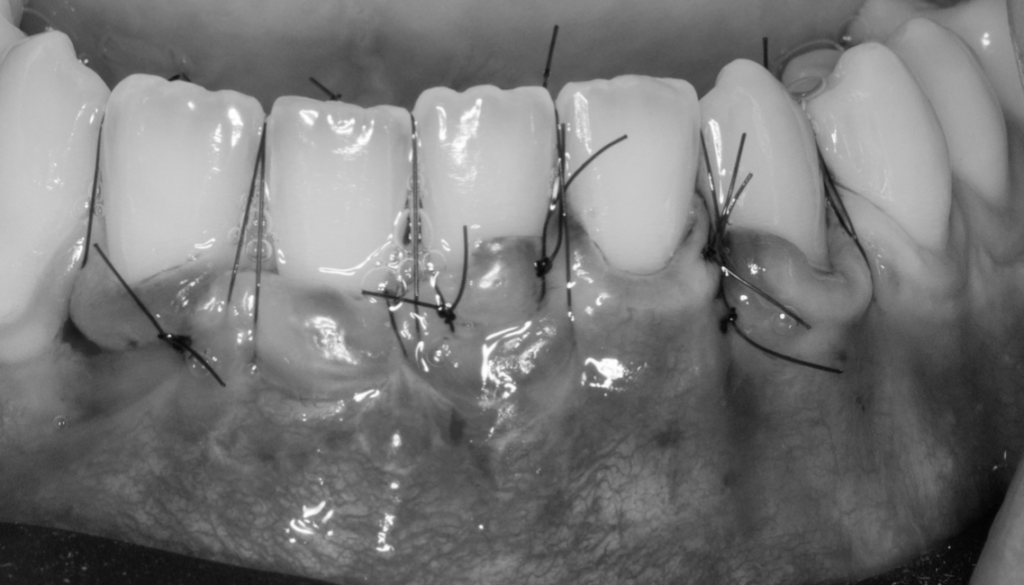

ITC (Injerto tejido conectivo libre desepitelizado de paladar) + tunelización

Fotografías del proceso: